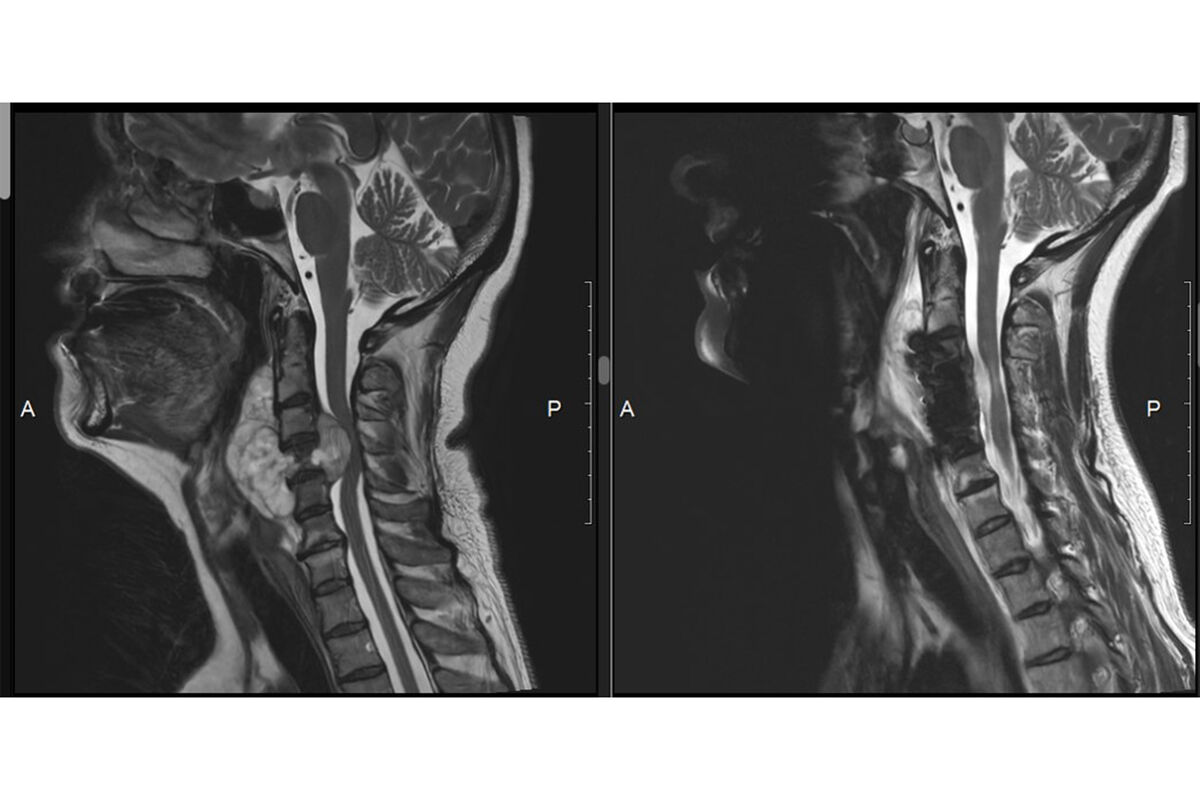

Во время обследования у женщины обнаружили большую опухоль в шейном отделе позвоночника, которая разрушила один из шейных позвонков и сдавила спинной мозг.

Женщине оперативно провели операцию. Специалисты удалили опухоль и стабилизировали работу позвоночника. Так как один из позвонков был разрушен, на его место установили имплантат.